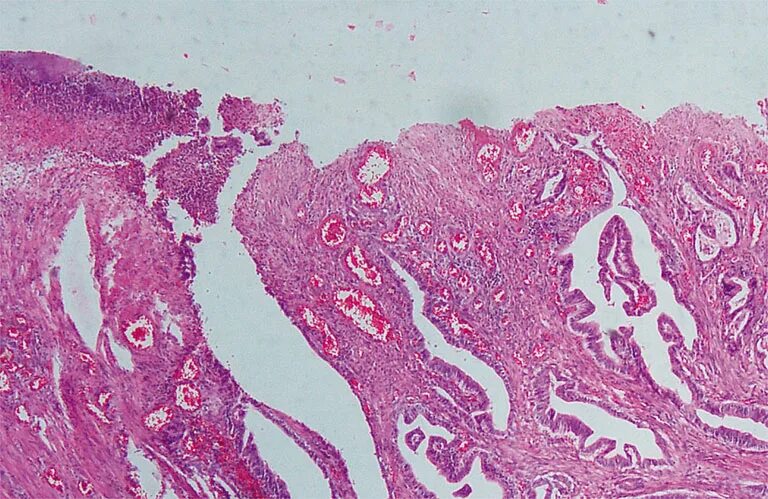

Высокодифференцированная аденокарцинома кишки